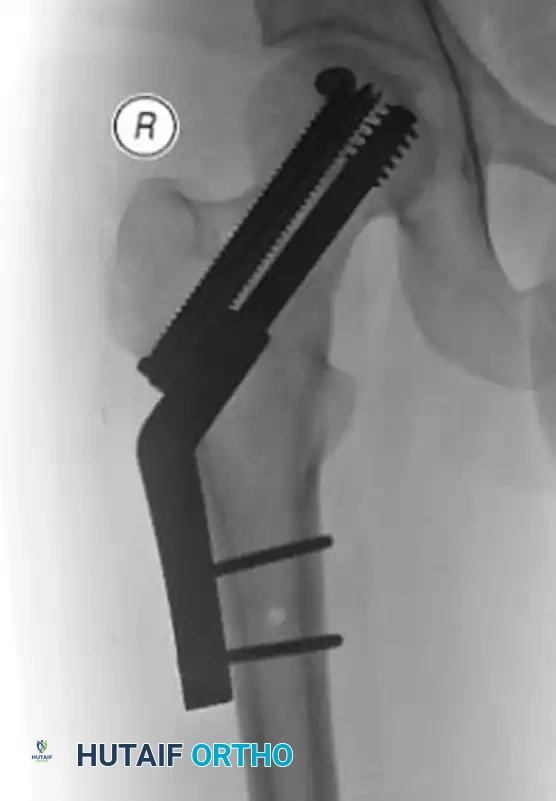

When malreduction is identified early in a physiologically robust patient, revision open reduction and internal fixation (ORIF) may be attempted, often utilizing more rigid constructs such as proximal femoral locking plates to achieve absolute stability.

Figure: Postoperative radiograph following revision ORIF, demonstrating improved alignment.

Figure: Orthogonal view of the revision ORIF utilizing a fixed-angle device to prevent recurrent varus collapse.